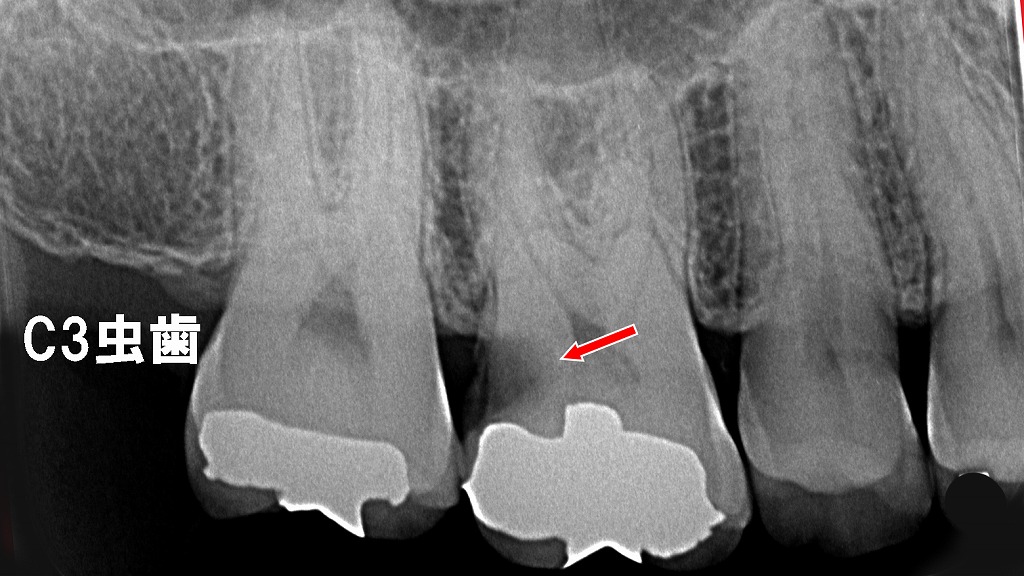

赤矢印の部分は、上顎6番遠心に発生したC3虫歯を示しています。レントゲン上では、虫歯が象牙質の深部まで進行し、歯髄(神経)に近接あるいは到達していることが確認できます。この段階では強い痛みが出やすく、根管治療が必要となるケースが多くなります。早期発見・早期治療の重要性を示す典型的な所見です。